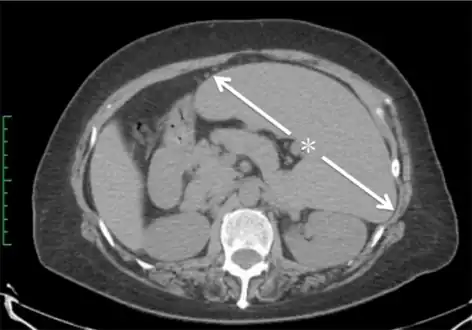

CT scan in a patient with chronic lymphocytic leukemia, showing splenomegaly. Yellow arrows point at the spleen.

Abdominal CT is the most accurate and spleen need to be larger 2-3 times to be palpable below the costal margin in physical examination that can help in diagnosis.